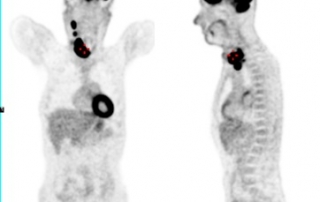

TEP-FDG masse médiastinale hypermétabolique isolée